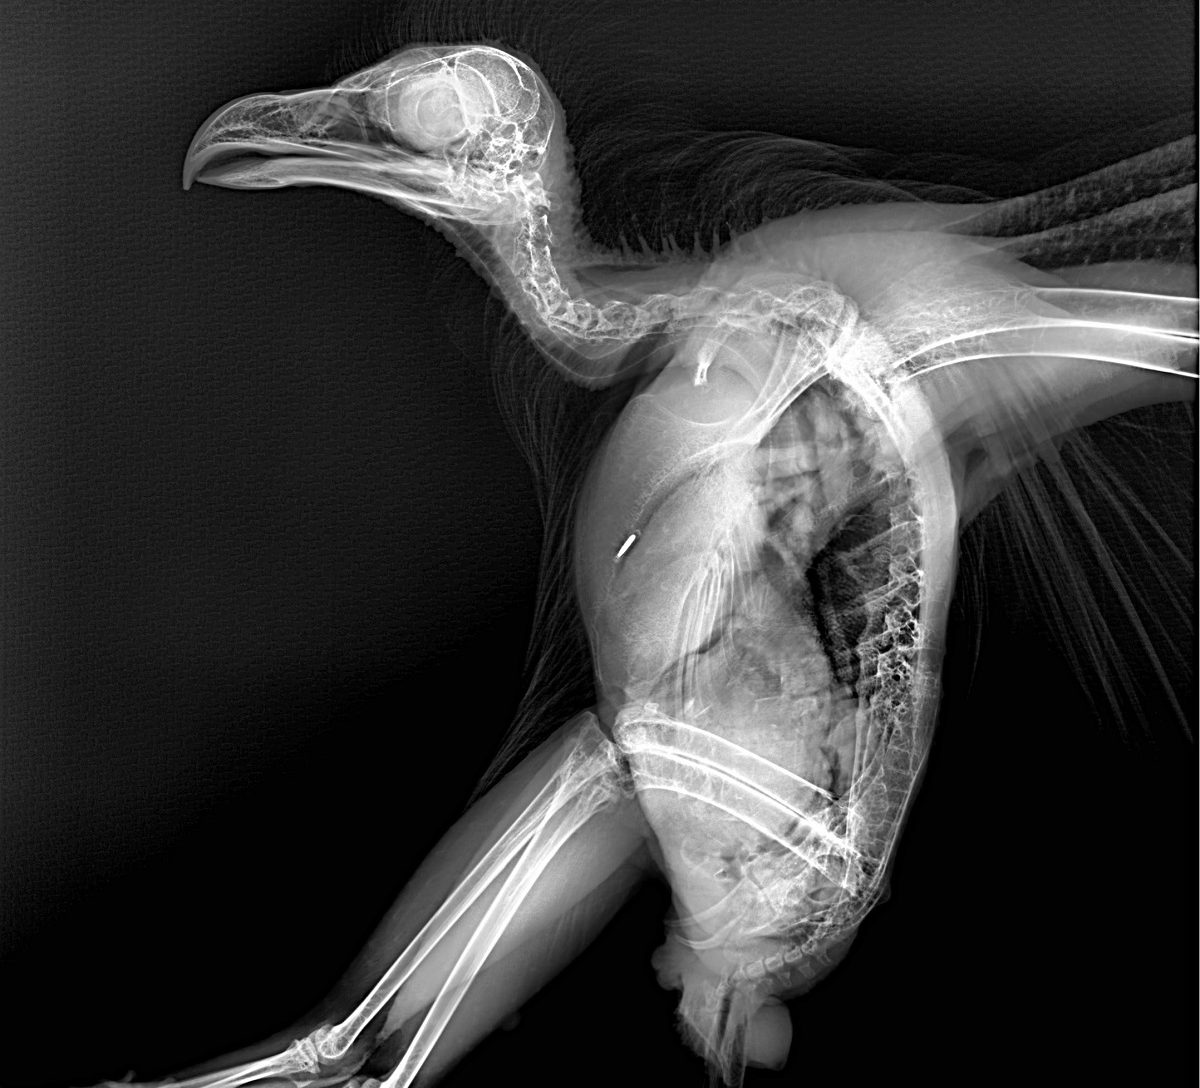

Este procedimiento diagnóstico permite a nuestros expertos brindar una excelente atención médica. Al exponerlos a los rayos X, el equipo puede tomar fotografías de las partes óseas internas de los animales, comprobando la existencia de lesiones o enfermedades que a simple vista no podrían ser identificadas.

Pero, ¿cómo se toma una radiografía de un tigre de Sumatra, de un cálao Gorginegro, un flamenco o un encantador armadillo de tres bandas?

Como indica Rosa Martínez, veterinaria en Bioparc Fuengirola, “los animales considerados peligrosos para su manejo requieren de un proceso de anestesia previo a la toma de radiografías. Por ejemplo, un tigre de Sumatra no va a prestarse voluntariamente para realizar el estudio. Es necesaria una inmovilización previa, normalmente con anestesia general, para realizar estas pruebas diagnósticas, esenciales para asegurarnos que todo está bien”.